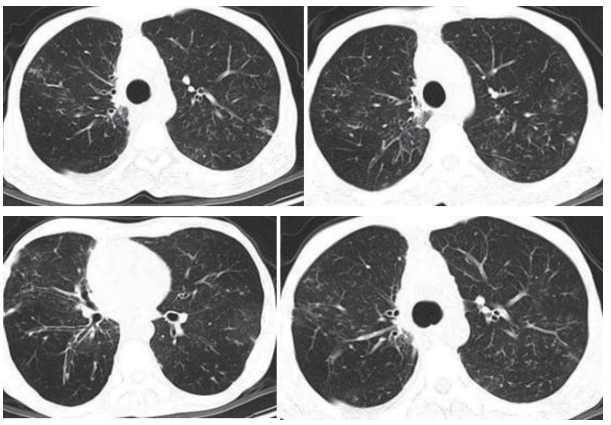

2月前患者自觉活动后气短明显加重,复查胸部CT示双肺炎性病变可能、较前部分新发,范围扩大(图1)。遂于我院住院治疗,气管镜肺泡灌洗液检出诺卡菌、黄曲霉菌,予以复方磺胺甲噁唑联合伏立康唑抗感染治疗1月余,咳嗽、咳痰症状减轻,呼吸困难基本改善。复查胸部CT示双肺炎症病变明显吸收(图2),出院后继续口服复方磺胺甲噁唑伏立康唑抗感染治疗。

图2 胸部CT(2024年8月)